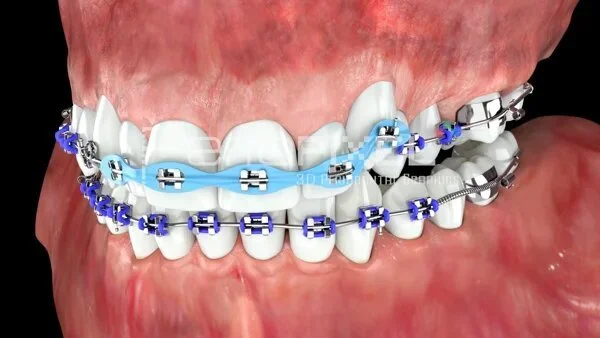

Tratamiento de Ortodoncia

El tratamiento de ortodoncia corrige la posición de los dientes y la mordida, mejorando la función y la estética de la sonrisa.

Brackets Metalicos

Los brackets metálicos son el sistema de ortodoncia tradicional, efectivo, resistente y accesible para alinear los dientes.

Brackets Zafiro

Los brackets de zafiro ofrecen un tratamiento estético y discreto, siendo translúcidos y resistentes.